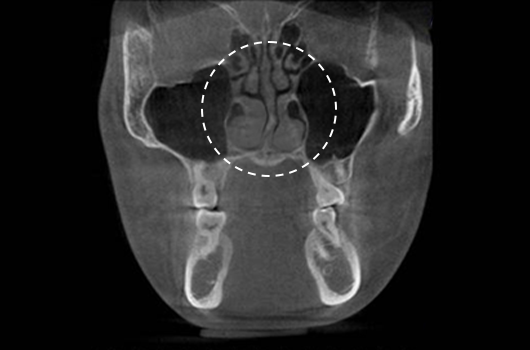

Importance of 3D-CT Scan in Rhinoplasty

During every consultation for rhinoplasty, Braun Plastic Surgery Clinic uses 3D-CT scan to analyze the following issues in three dimensions: A precise surgical plan can be established, and potential side effects reduced by thoroughly understanding the size, shape, and asymmetry of the invisible portions of the nose and the nearby anatomical structures prior to surgery.

2. Diagnosis of deviated nose and septal deviation

Diagnosis of deviated nose and septal deviation

3. Analysis of the width and asymmetry of the nasal bone

Analysis of the width and asymmetry of the nasal bone

4. Diagnosis of inferior turbinate asymmetry and surgery for nasal obstruction

Diagnosis of inferior turbinate asymmetry and surgery for nasal obstruction